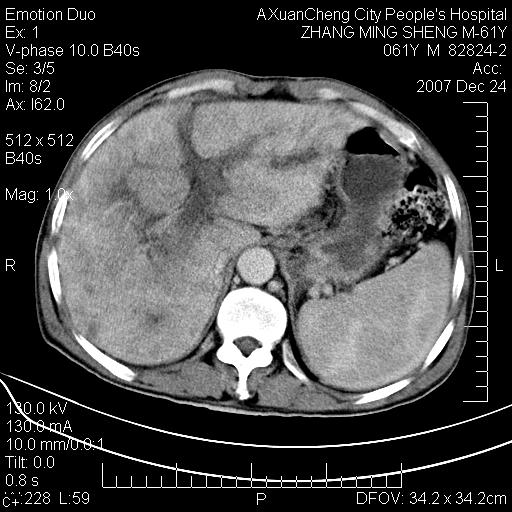

标题: CT11031:M61Y,胰腺占位

大家侃侃门静脉和胆管系统怎么回事,肝内转移?

胰腺癌肝转移

胰腺体部稍宽,其内小片样低密度灶性质?

2,肝内多发结节状低密度占位,伴门脉及肠系膜上v栓子形成.考虑a;门脉及肠系膜上v血栓后肝改变.b;弥漫型肝癌伴门脉及肠系膜癌栓.

肝硬化,门脉高压,脾肿大;弥漫性肝癌,肝内、门脉、腹膜后淋巴结转移,肝内外胆管扩张,胰头区占位,建议mr检查

胰腺癌伴肝内转移;门脉、肠系膜上v癌栓形成。

考虑为:胰腺癌伴肝脏转移、腹膜后淋巴结转移,门静脉及肠系膜上静脉瘤栓形成。

胰体尾癌伴肝内转移,门静脉及肠系膜上静脉瘤栓形成.